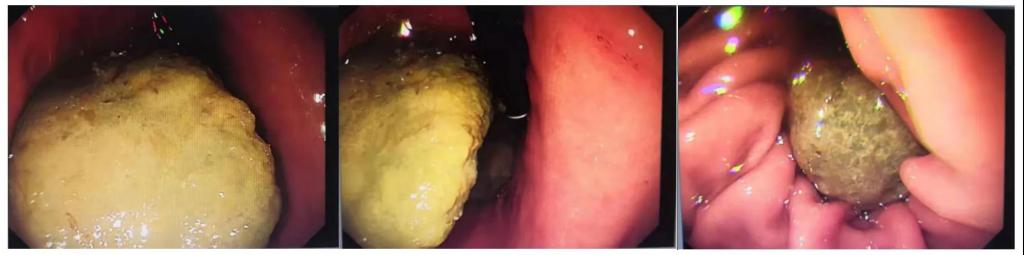

胃镜显示胃内结石较大,患者已无法进食,立即收住入院。

该患者喝了6天可乐后,腹部胀痛症状缓解,腹部无明显压痛,给予安排复查胃镜,并做好了内镜下碎石的准备。结果还是让大家很欣慰的,经过积极治疗,患者胃内结石已完全溶解,溃疡也较前明显好转。